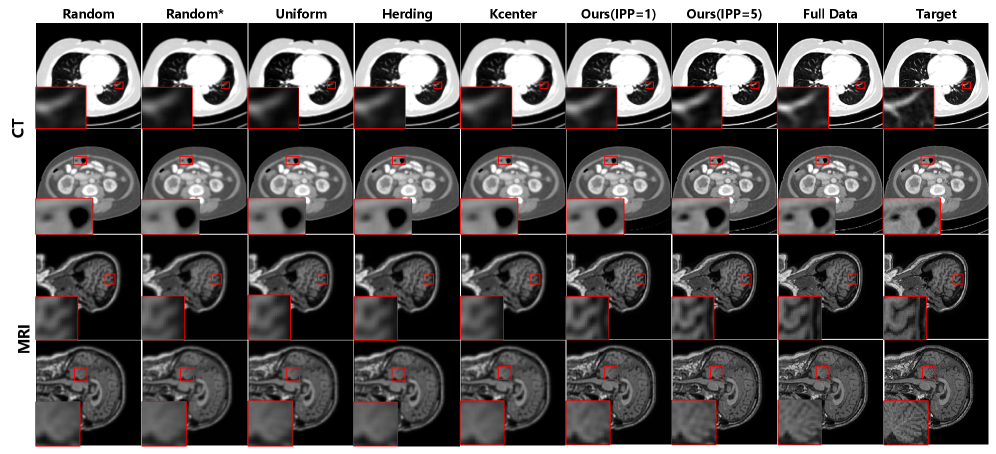

Refer to caption

Figure 4: Qualitative super-resolution results of different algorithms with CT and MRI modality. The display window for the first row is [-950, 50] HU, while for the second row is [-290, 310] HU.

Super-Resolution in the CT Modality. For the CT modality, quantitative results are shown in Tab. 1. Overall, coreset selection methods achieve similar performance at the same NRI, with Herding and K-Center demonstrating slightly better effectiveness and stability. Compared to these methods, our proposed method consistently outperforms them across all settings, clearly validating its effectiveness, and achieves the best performance when IPP=5. In our method, increasing IPP leads to noticeable improvements in performance, while also yielding more stable results. As NRI increases, incorporating more information, all methods exhibit performance improvements. Ultimately, our proposed method achieves the best super-resolution results, with a PSNR of 34.57 dB and an SSIM of 92.83, demonstrating our effectiveness. The qualitative results are shown in Fig 4. It can be noticed that our method significantly outperforms existing approaches on the CT super-resolution task, recovering anatomical details that more closely resemble the targets.

Super-Resolution in the MRI Modality. For the MRI modality, quantitative results, asillustrated in Tab. 1, show a trend similar to that observed for CT. The performance of coreset selection methods is comparable, while our method consistently outperforms them and achieves the best results. As NRI increases, all methods improve. Remarkably, our approach reaches up to 97% of the PSNR and SSIM performance obtained with the full dataset. The reason lies in that our method effectively injects patient-specific anatomical and training information into the distilled dataset, as described in the previous section. In terms of qualitative results, utilizing the synthetic samples distilled by our approach leads to images with improved visual fidelity and anatomical detail, showing a closer resemblance to the target images, as shown in Fig. 4.